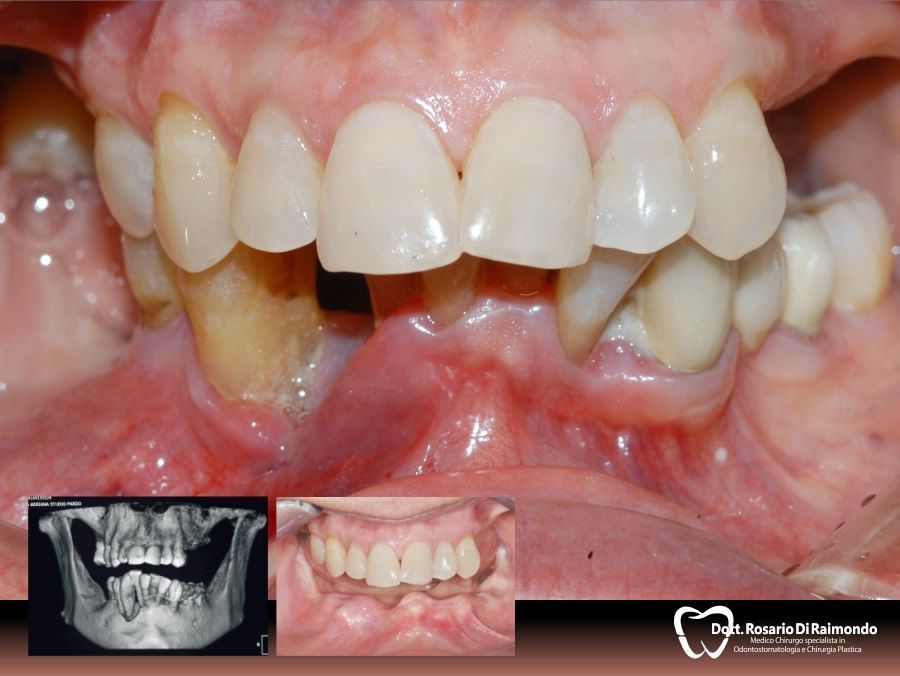

Casi Trattati

Di seguito riportiamo alcune fotografie di casi di Implantologia già trattati.